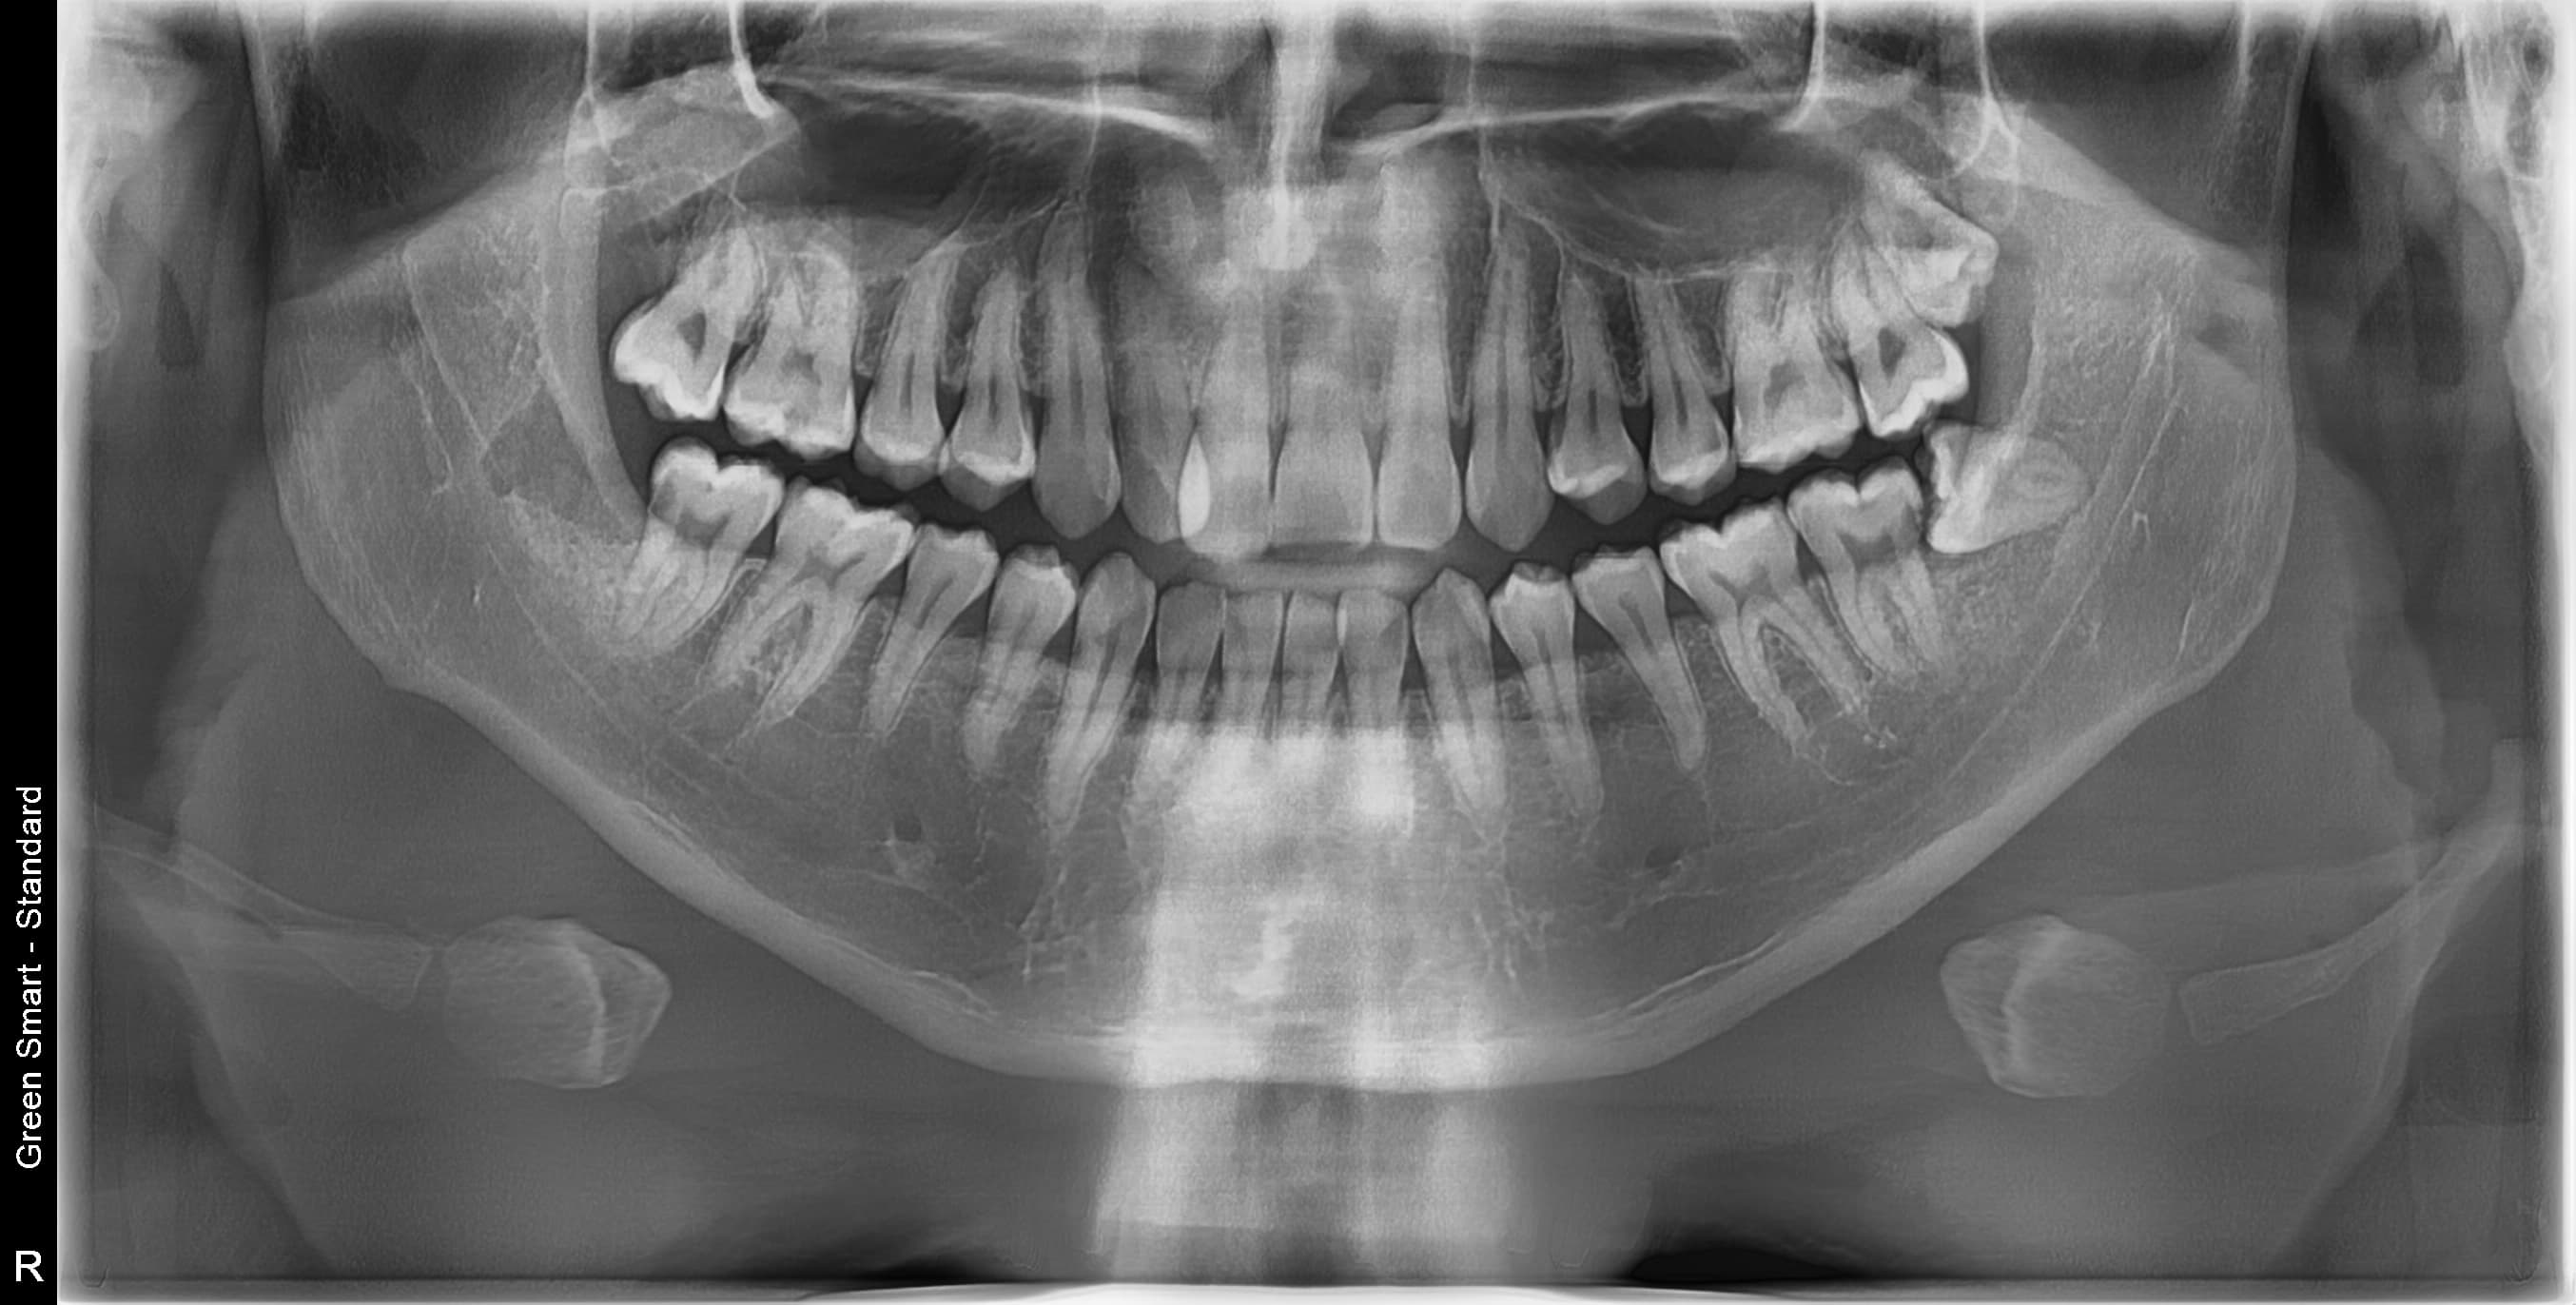

복잡한 매복 사랑니 — 잇몸 속 깊이 묻혀있어도 OK

신경 근접 사랑니 — 신경 손상 걱정 없는 안전한 발치

수평 매복 사랑니 — 옆으로 누워있는 어려운 케이스도 가능

조선대 치과병원 외래교수 역임 원장이

직접 안전하게 해결합니다